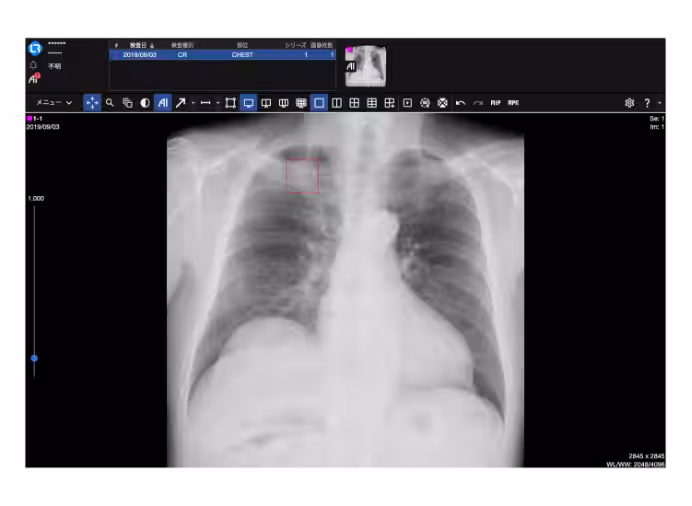

今回の連携は、胸部X線に特化した「EIRL Chest XR」や「EIRL Chest Nodule」、さらには頭部MRAに対応した「EIRL Brain Aneurysm」の利用が可能です。これによって、クラウドPACSを利用する医療機関にとって、AIを活用した診断支援が容易になるのです。特に「EIRL Brain Aneurysm」は2025年に偽陽性を低減した新モデルが登場予定で、さらなる医療の質向上が期待されます。

画像1